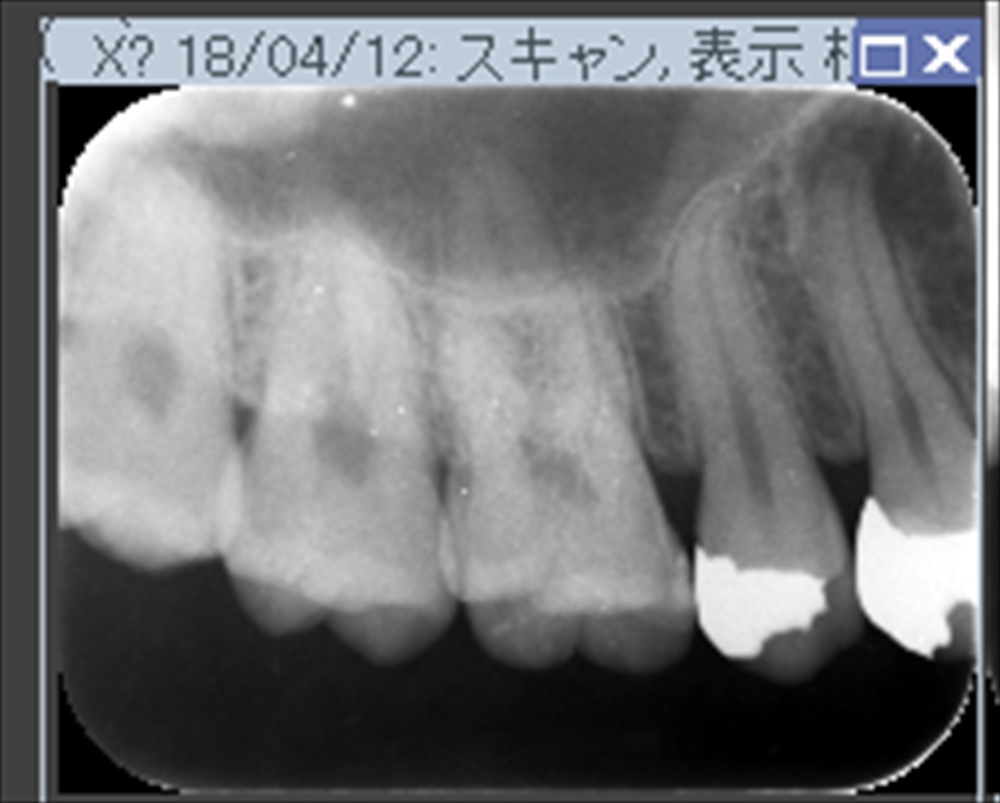

術前

術後